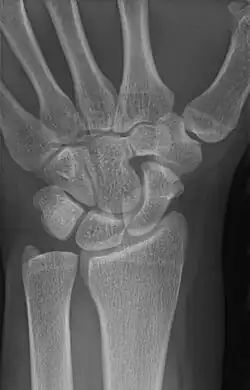

An example of a lunotriquetral coalition, the most commonly fused carpal bones

The lunate and triquetral bones are the most common carpal bones to fuse together, resulting in a lunotriquetral coalition in 1% of people. 60% of patients with a lunotriquetral coalition will have it bilaterally.[1] Among isolated incidents the capitate and hamate bones are the next most common to fuse followed by the pisiform-triquetrum, trapezium-trapezoid, scaphoid-capitate, and triquetrum-hamate.[3]